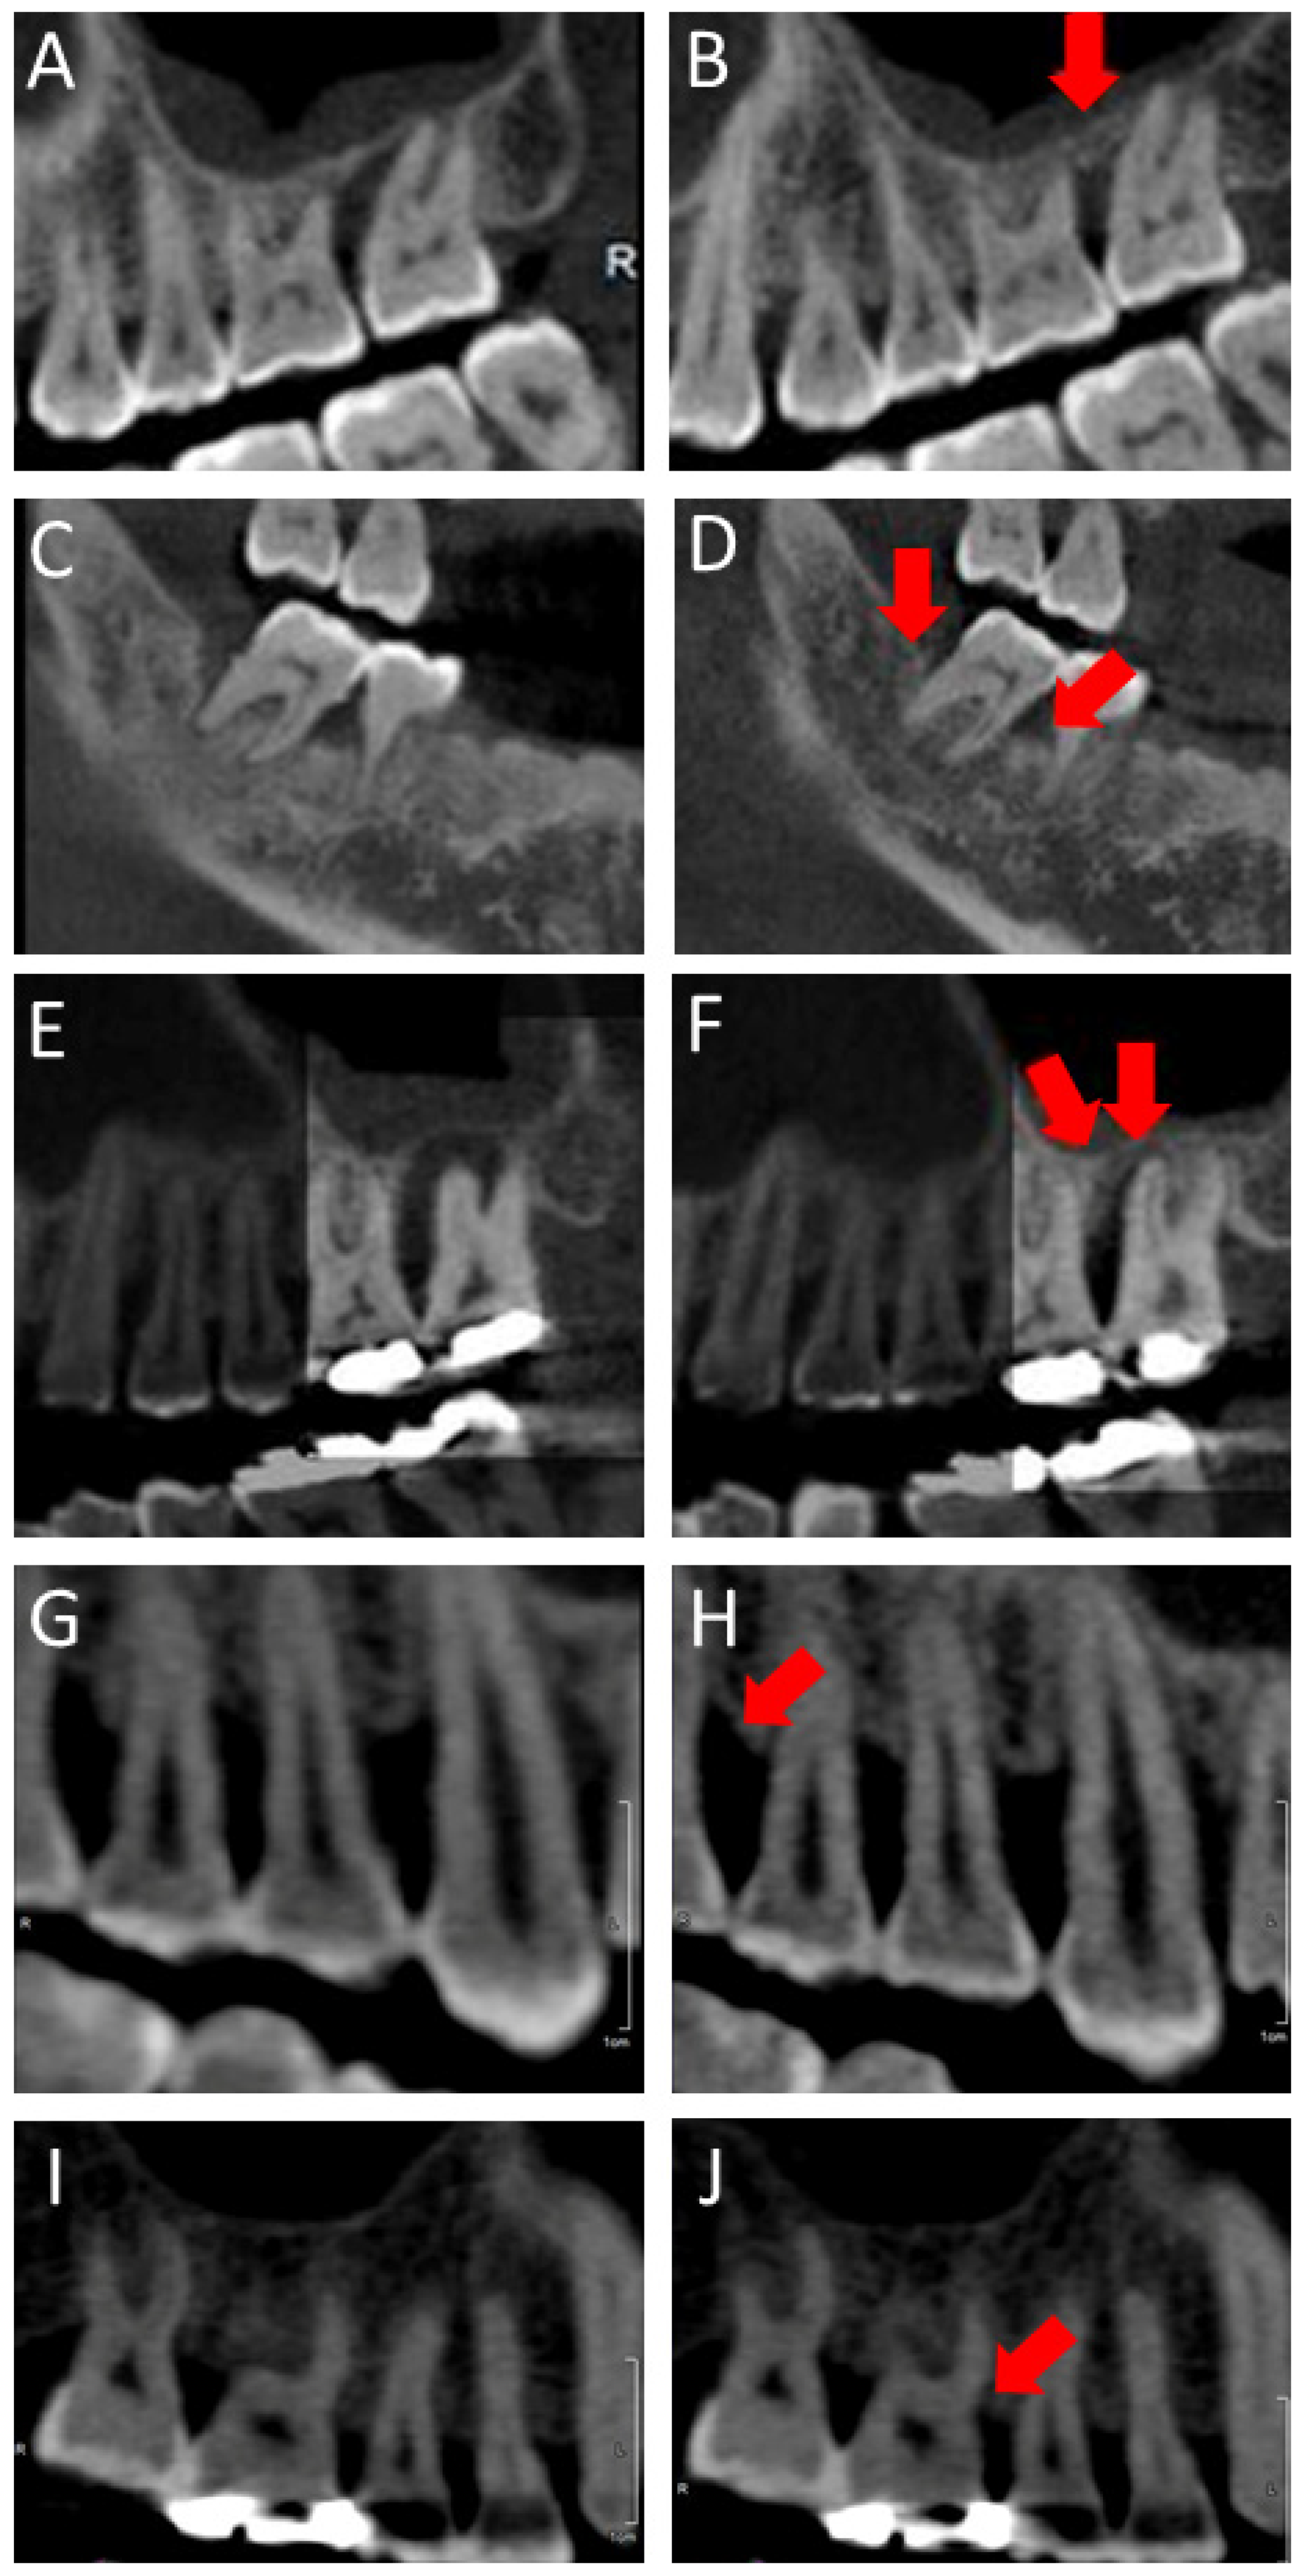

:1. Introduction

2.4. CBCT Taking and Maintenance Care (3 and 6 Months)

2.5. Radiographic Evaluation and Bone Height Measurement